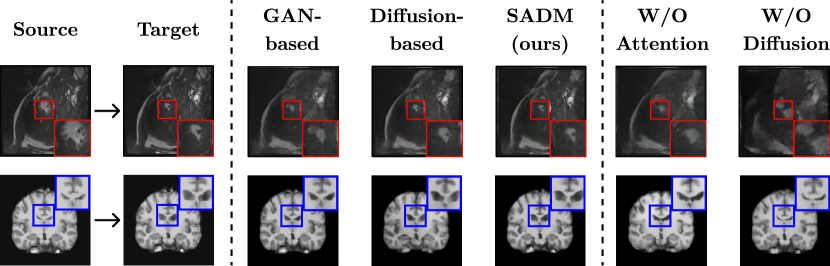

In this section, we show the effectiveness of our proposed SADM in medical image generation on one public 3D longitudinal cardiac MRI dataset and one simulated 3D longitudinal brain MRI dataset. We compare our work with GAN-based [4] and diffusion-based [12] baselines quantitatively and qualitatively. Finally, an ablation study of our model components with various settings for the input sequence is presented.

Refer to caption

Figure 4: Qualitative comparison between baselines, proposed SADM, and ablated models for single image setting. GAN-based model [4] uses a UNet-based GAN model to synthesize MRI frame, and diffusion-based model [12] uses a diffusion model with a deep registration model to register one frame to another. W/O Attention model is SADM with only the diffusion model, while W/O diffusion model is SADM with only the attention module. Red boxes indicate blood pool regions and blue boxes indicate ventricle regions.

A qualitative comparison is presented in Fig. 4, and a quantitative comparison is presented in Table 1. For cardiac image generation, our proposed SADM shows a better depiction of the blood pool (red box) compared to the baseline methods. Also, other areas surrounding the blood pool, such as the myocardium and ventricles, are also synthesized with higher fidelity. For brain image generation, the ventricular regions (blue box) synthesized by SADM are more crisp compared to baselines, and the cortical surface is synthesized more accurately. Then, we perform a quantitative comparison by calculating the structural similarity index (SSIM), peak signal-to-noise ratio (PSNR), and normalized root-mean-square deviation (NRMSE) between the target and the synthesized ES frame. Our model outperforms the GAN-based method [4] by 313%similar-to3percent133\sim 13\% in each metric while slightly outperforming the diffusion-based model [12]. It is worth noting that the diffusion-based baseline uses a source image and a reference image for registration, whereas we only use the source image as input. Although our proposed SADM is capable of working with a single image, it is designed to perform even better with a sequence of images, as shown in the next section.